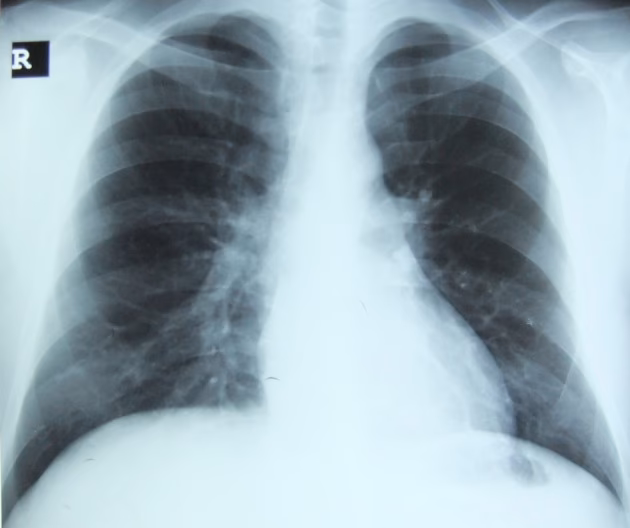

At diagnosticere en atypisk infektion kan være en udfordring. Lægen vil ofte basere sin mistanke på det kliniske billede: en patient med en langvarig, tør hoste og generel utilpashed, hvor en fysisk undersøgelse ikke afslører tegn på alvorlig lungebetændelse. Specifikke tests som blodprøver (serologi), der leder efter antistoffer, eller podninger fra svælget (PCR-test) kan bekræfte diagnosen, men disse anvendes ikke altid ved mild sygdom.

Begreberne bruges ofte i flæng, fordi de forårsages af de samme organismer. Teknisk set er bronkitis en betændelse i bronkierne (luftvejene), mens lungebetændelse (pneumoni) er en infektion i selve lungevævet (alveolerne). "Gående lungebetændelse" er en uformel betegnelse for en mild lungebetændelse, der ikke kræver sengeleje. En atypisk infektion kan forårsage begge dele, og grænsen kan være flydende.

Du bør kontakte din læge, hvis din hoste varer mere end tre uger, hvis du har høj feber, åndedrætsbesvær, brystsmerter, hoster blod op, eller hvis du generelt føler dig meget syg. Dette er vigtigt for at udelukke en mere alvorlig tilstand som lungebetændelse og sikre, at du får den korrekte behandling.